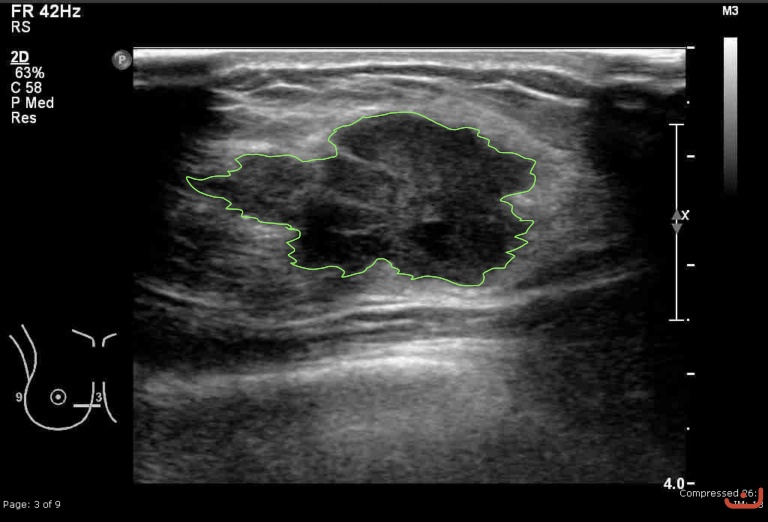

Malignant solid mass